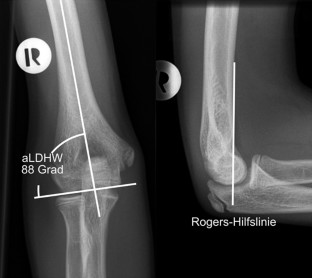

Die Pseudarthrose des kindlichen Condylus radialis humeri mit posttraumatischem Cubitus valgus stellt nach inadäquater Behandlung eine ernsthafte Komplikation dar. Wir berichten über einen damals 14-jährigen männlichen Patienten, der nach konservativer Frakturbehandlung des Condylus radialis humeri eine zunehmende Fehlstellung im Sinne eines Cubitus valgus entwickelte. Nach Durchführung einer Schraubenosteosynthese wurde nach gesicherter Konsolidierung eine erfolgreiche suprakondyläre Domosteotomie vorgenommen, die zur Beschwerdefreiheit und freien Beweglichkeit des Ellenbogengelenks führte.

Non-union of the pediatric lateral humeral condyle following post-traumatic cubitus valgus is a severe complication after inadequate treatment. We report on a then 14-year-old male patient who developed an increasingly defective position in terms of cubitus valgus after conservative treatment of a lateral humeral condyle fracture. After performing screw osteosynthesis and achieving consolidation, a successful supracondylar dome osteotomy was performed which led to relief from pain and free range of motion of the elbow joint.

Abb. 3